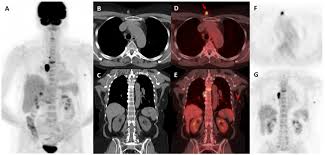

An FDG PET CT scan uses a glucose-based radioactive tracer known as FDG. Since cancer cells and certain infections consume more glucose than normal tissues, the scan highlights abnormal metabolic activity in the body. The Best FDG PET CT Scan in AIIMS can detect disease even at an early stage, when symptoms may not be obvious.

Advanced Imaging Technology for Reliable Results

The Best FDG PET CT Scan in AIIMS is backed by state-of-the-art PET CT scanners that provide high-resolution images and precise metabolic mapping. Modern technology allows doctors to identify even small lesions that might be missed on conventional imaging.